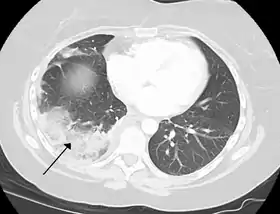

الرَّضَّة الرئوية كدمةٌ تحدث بسبب الصدمة الصدريّة، تؤدِّي الرضَّة إلى نزف الأسناخ، مما سيؤدي إلى امتلائها بالسوائل وبالتالي إعاقة التنفُّس، وقد تكون هذه الحالة معتدلة أو شديدة. قد تتأثر وظيفة الرئتين كذلك بالانضغاط من السوائل في حالة انصباب السائل الجنبي في الجوف الجنبي، أو مواد أخرى كالهواء في حالة استرواح الصدر، أو الدم في حالة الصدر المُدمى، أو لأسباب أخرى نادرة. تُستخدم الاستقصاءات كالأشعة السينية للصدر أو التصوي المقطعي المحوسب، أو قد تتطلَّب الحالة إدخال أداة تصريف جراحية حتى يتم التعرُّ على السبب ومعالجته.[44]

يمكن أن ينشأ سرطان الرئة إما مباشرة من أنسجة الرئة أو كنتيجة لانبثاث من جزء آخر من الجسم. هناك نوعان رئيسيَّان للورم الأوليّ إما صغير الخلايا أو غير صغير الخلايا. يُمثِّلُ التدخين عامل الخطر الرئيسي لسرطان الرئة. وعندما يتمّ التعرُّف على سرطان يتمّ تقييمه باستخدام التصوير المقطعي المحوسب وأخذ خزعة (عينة من الأنسجة). قد يُعالج السرطان عبر الإزالة الجراحية للورم أو المعالجة الشعاعية أو المعالجة الكيميائية أو قد يشتمل على عدة وسائل من السابقة، أو قد يقتصر على السيطرة على الأعراض.[44] جديرٌ بالذكر أن استقصاء سرطان الرئة يُنصح به في الولايات المتحدة للسكان ذوي خطر الإصابة المرتفع.[53]